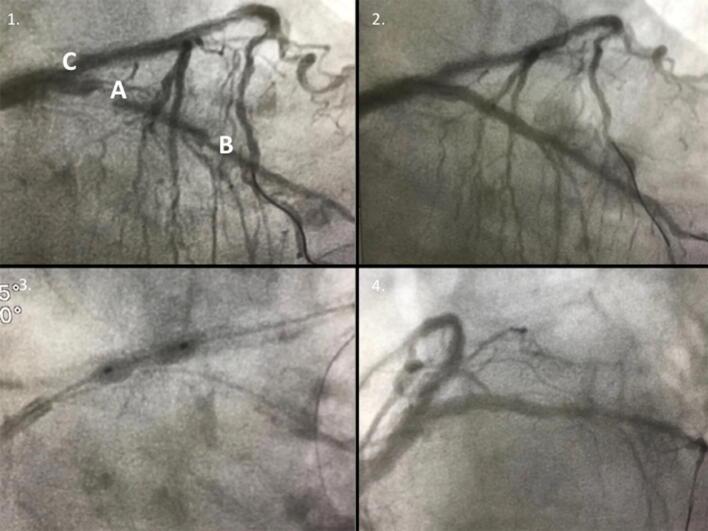

Complicated myocardial infarction in a 99-year-old lady in the era of COVID-19 pandemic: from the need to rule out coronavirus infection to emergency percutaneous coronary angioplasty.

Intern Emerg Med. 2020 Aug;15(5):835-839. doi: 10.1007/s11739-020-02362-8. Epub 2020 May 13.